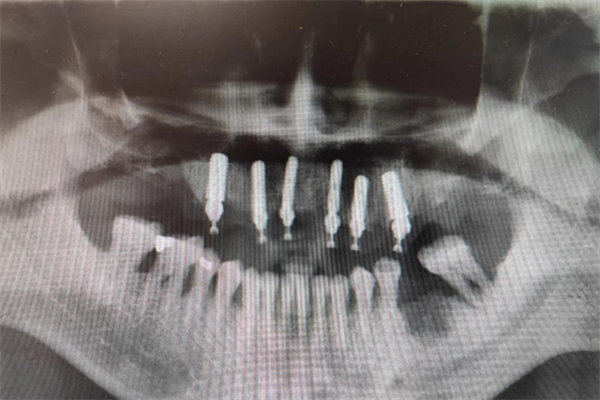

手術當天,楊濤主任帶領團隊在麻醉科的協(xié)助下,整個拔牙及種植過程十分順利。術后X線片顯示,種植體的植入深度、角度,高度都非常精準。

術后X線檢查,確認種植體植入位置